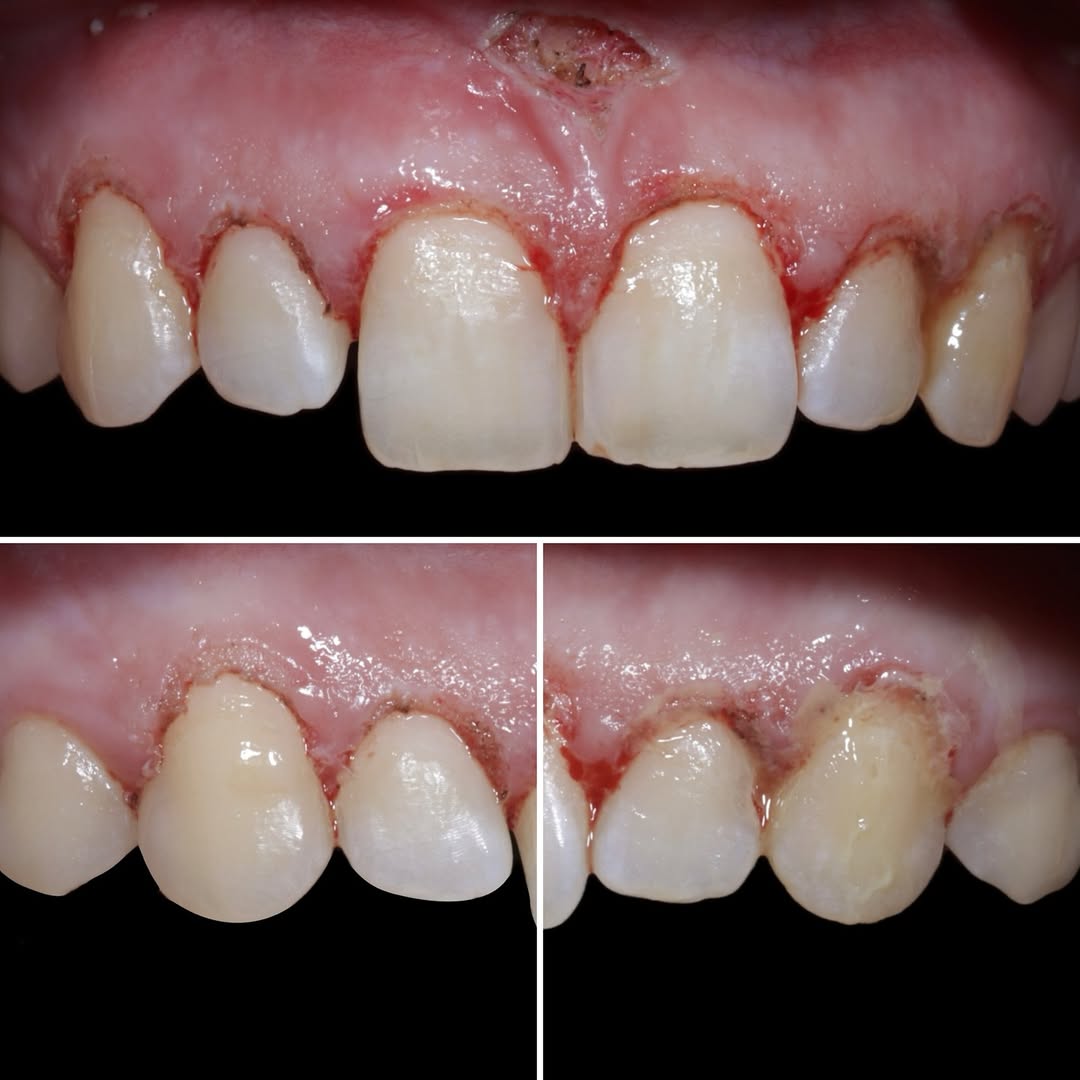

Ya se han realizado la extracción de los dientes 12, 11, 21, 22 para garantizar el cierre de tejidos blandos. El día de la cirugía, el alumno verá todo el procedimiento en una pantalla en directo en la sala de cirugía, ya que todo será realizado con un microscopio operatorio.

Se extraerán los

Los dientes remanentes del maxilar superior serán extraidos, se colocarán 5 implantes inmediatos flapless y 3 más con fresas de

Toda la cirugía se llevará a cabo con un microscopio operatorio y el paciente estará bajo sedación consciente.

Los alumnos pueden ver la cirugía en una pantalla, previa explicación del caso y posteriores explicaciónes durante la carga inmediata.